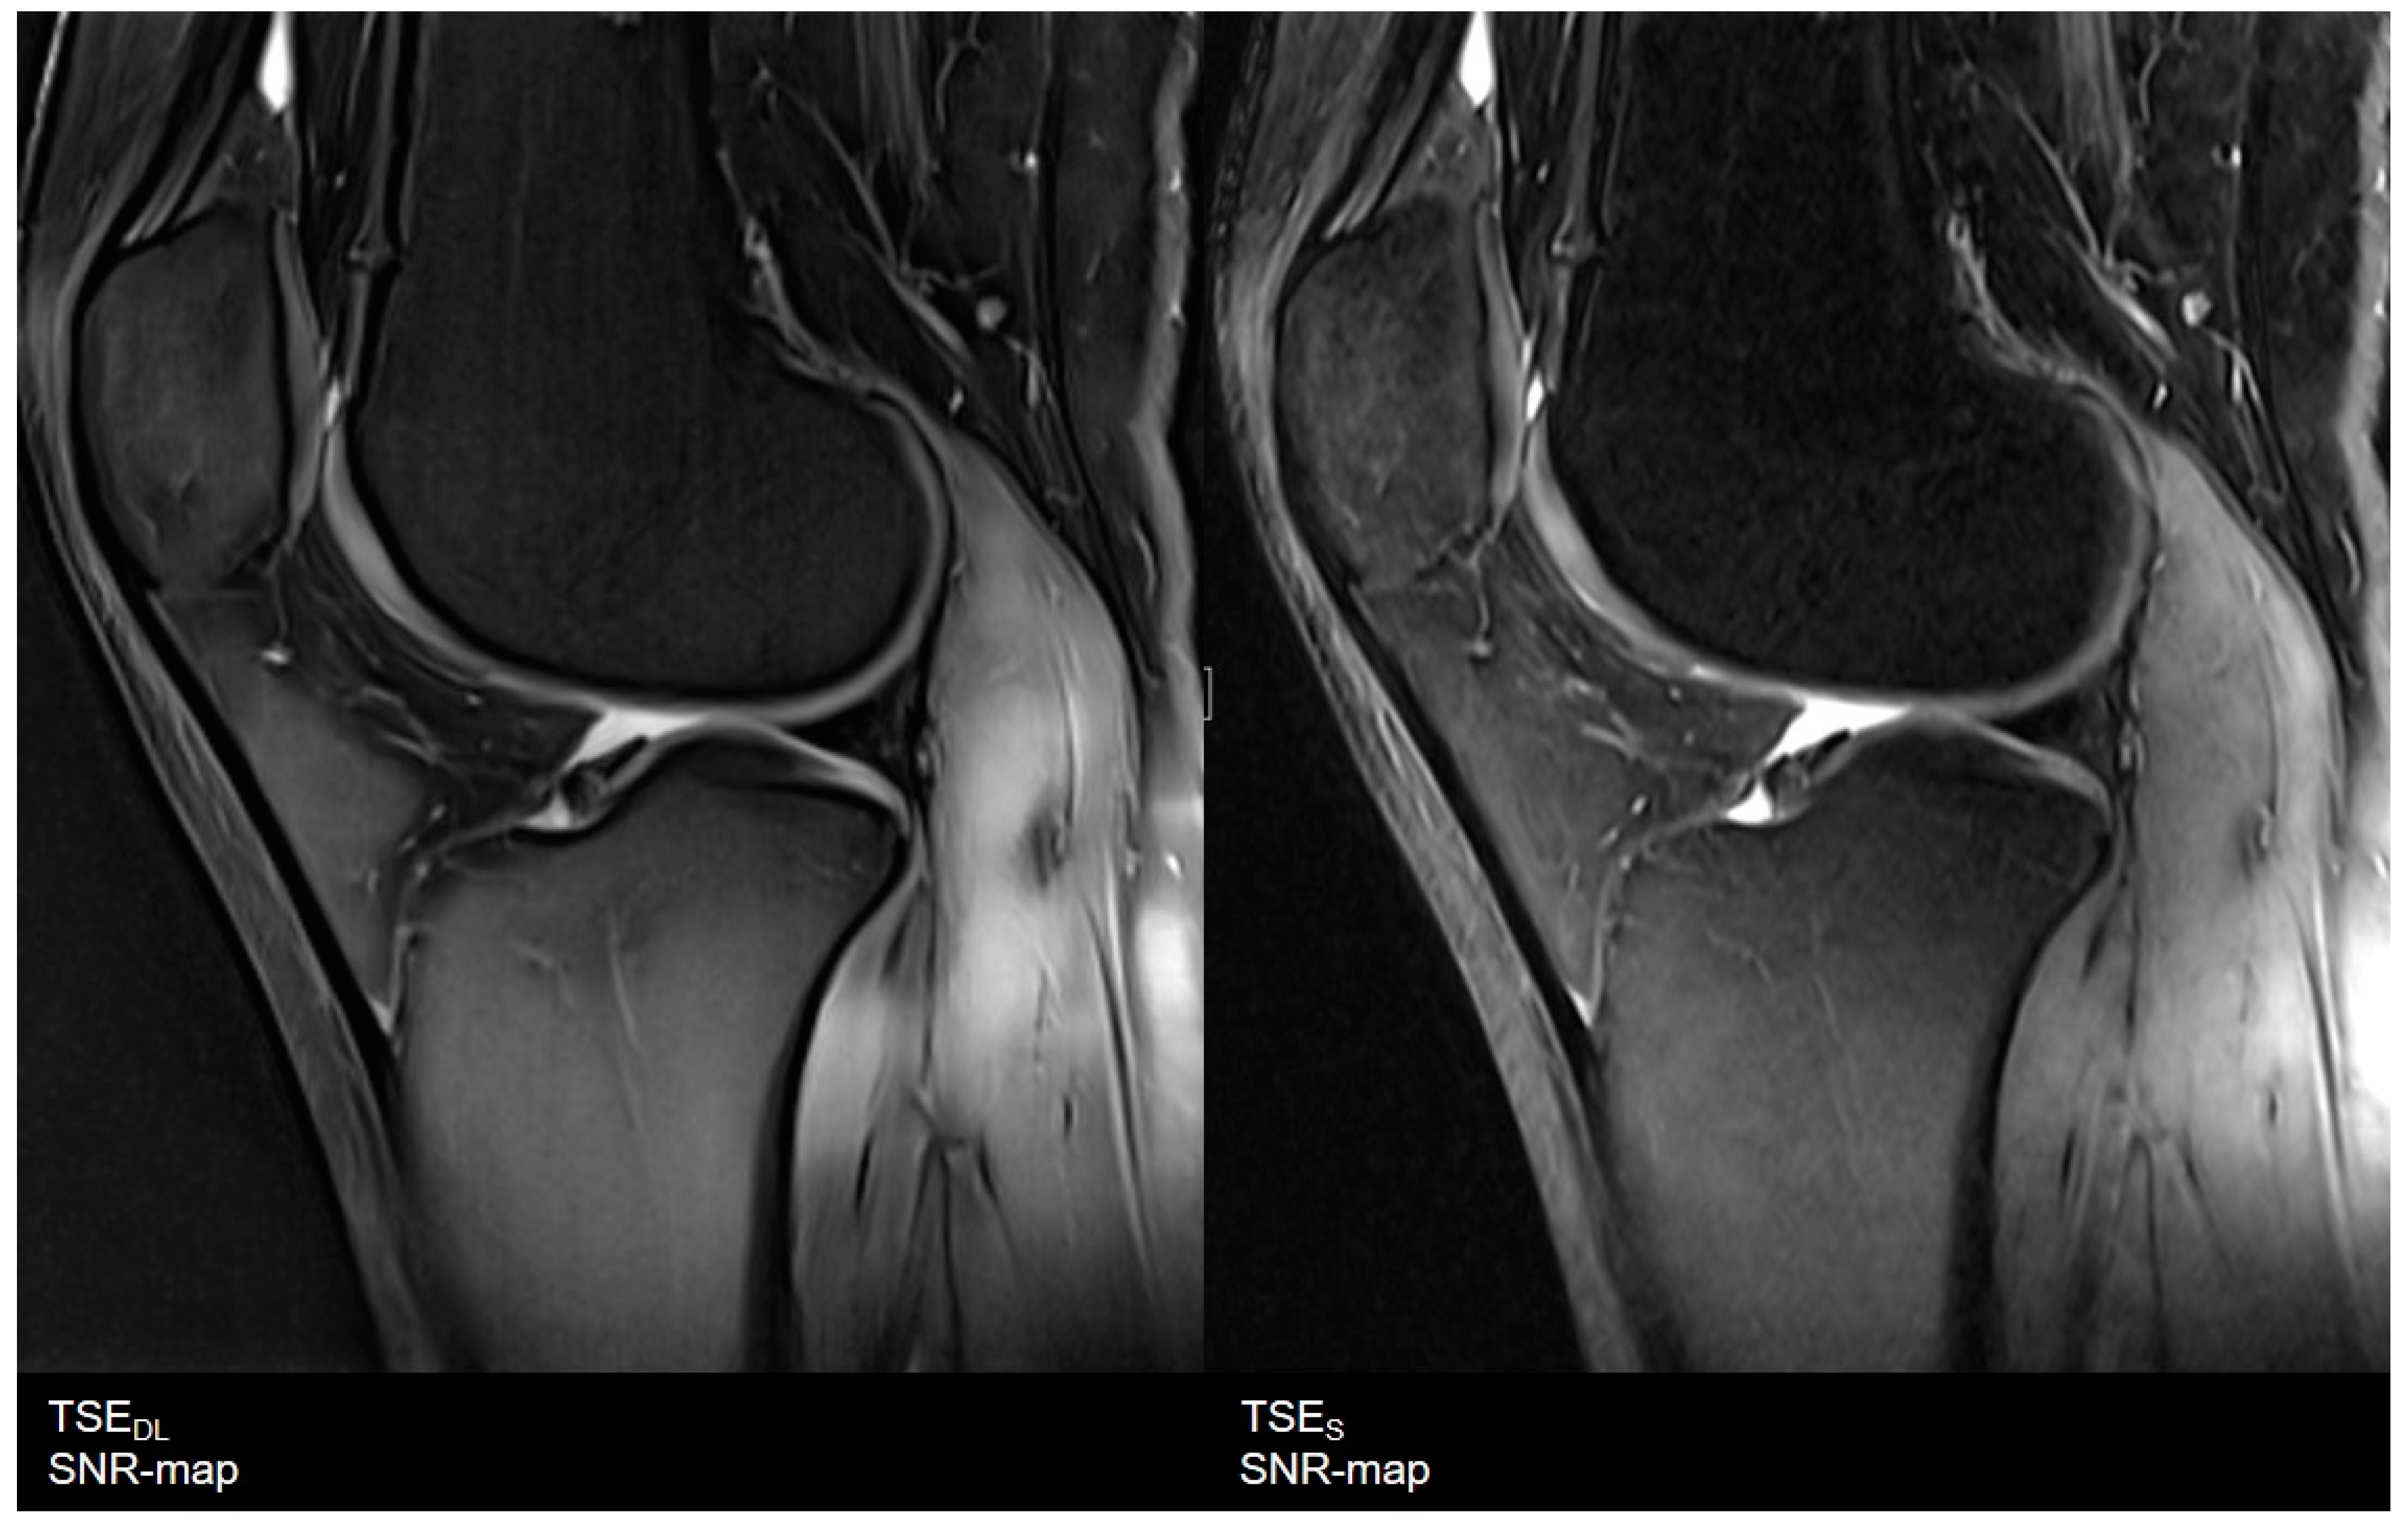

3.1. Assessment of Image Quality

- Robson, P.M.; Grant, A.K.; Madhuranthakam, A.J.; Lattanzi, R.; Sodickson, D.; McKenzie, C. Comprehensive quantification of signal-to-noise ratio andg-factor for image-based andk-space-based parallel imaging reconstructions. Magn. Reson. Med. 2008, 60, 895–907. [Google Scholar] [CrossRef] [Green Version]